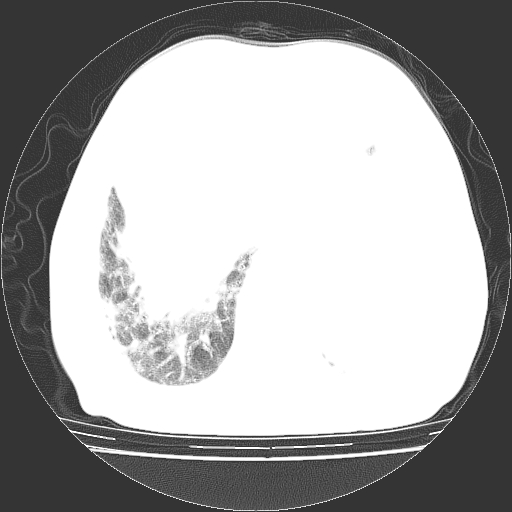

标题: CT25149:男,69岁,反复咳嗽、咳痰五年余,呼吸困难三天。 [打印本页]

男,69岁,反复咳嗽、咳痰五年余,呼吸困难三天。

慢支伴感染、肺气肿、肺心病

慢支伴感染、肺气肿、肺心病!支持!另:间质纤维化!

考虑慢性间质性肺炎并肺间质纤维化。

慢支伴感染、肺气肿、肺心病。双肺间质性改变(间质纤维化)。